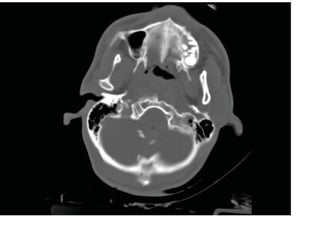

Anatomie- Niveau du

pons

• Violet - Sinus sphénoïde

• Jaune - angle

ponto- cérébelleux

• Rouge -

Pédoncule

cérébelleux

moyen

• Orange - Lobe

temporal

• Bleu - Quatrième

ventricule